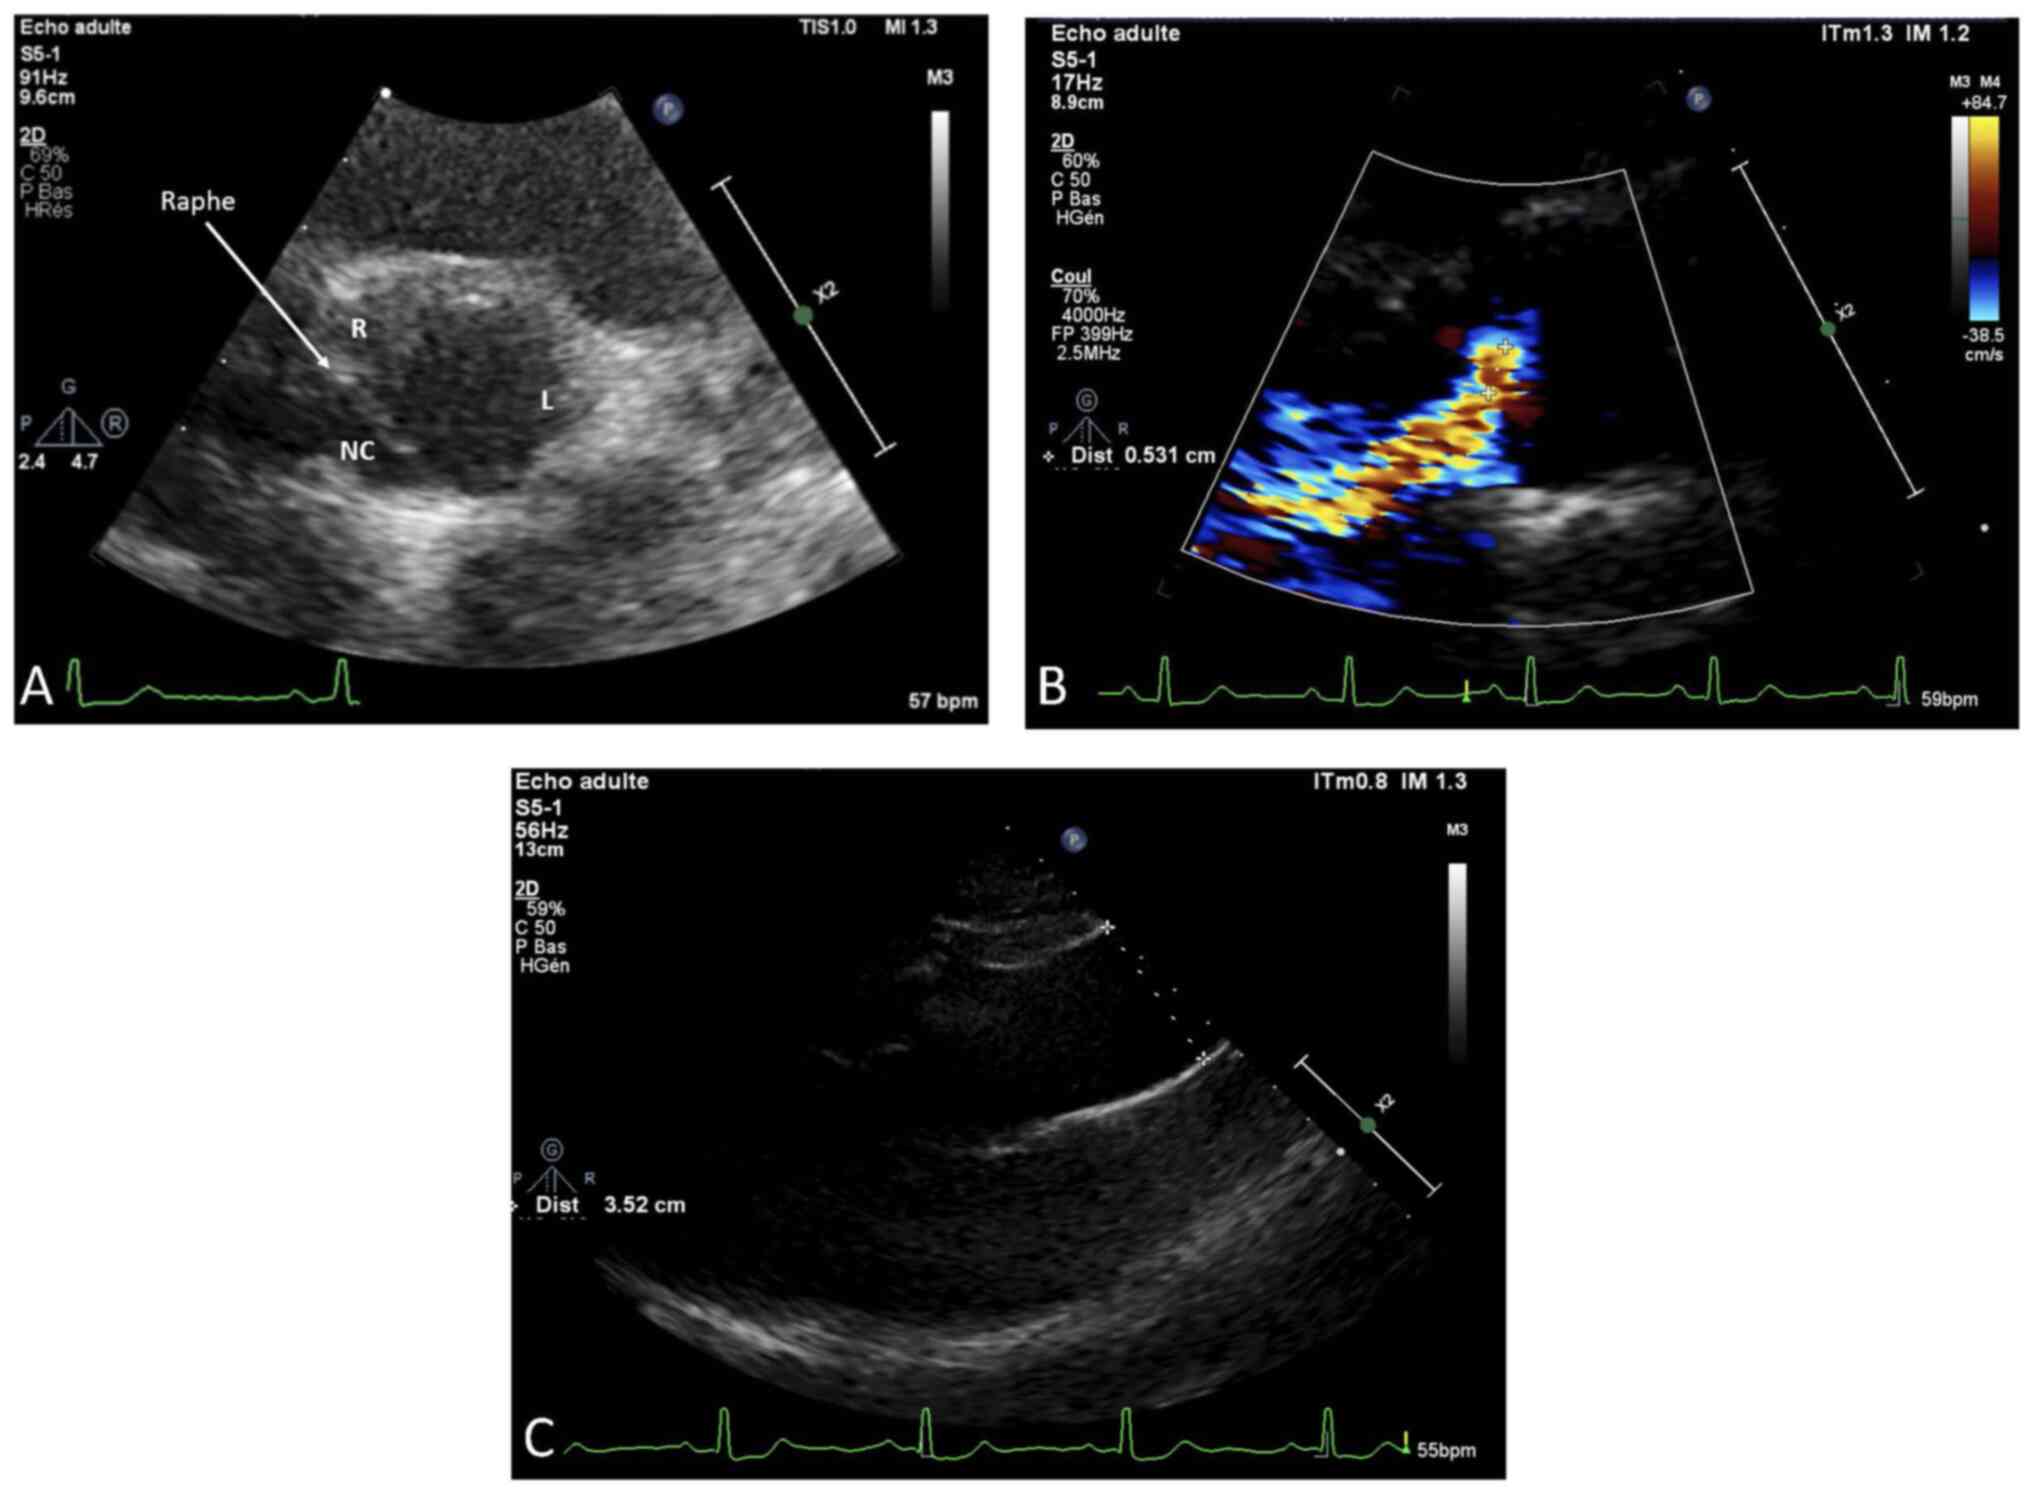

The patient is a female born to non-consanguineous parents. Her clinical presentation comprises features of VACTERL/HFGS syndrome including bicornuate uterus (double uterine cavities, double cervix), left arm agenesis, scoliosis, and BAV (Figs. 1 and 2). The patient was delivered at term with an upper left arm agenesis. Any imperforate anus nor anal atresia or tracheoesophageal fistula were noted in the patient's birth.

Her cardiac evaluation revealed a type 1 non-calcified BAV. Transthoracic echocardiography showed a normal left ventricular ejection fraction (LVEF=70%) with a slight diastolic LV dilation (Indexed end-diastole volume=108 ml/m2) and a raphe between the non-coronary and the right coronary cusps corresponding to a type I, N-L, according to the Sievers classification (Fig. 3A). A moderate aortic regurgitation was noted (ERO=20 mm2) due to a prolapse of the fused leaflet and a restriction of the left coronary cusp (Fig. 3B). The aortic valve leaflets were thin and un-calcified. There was neither BAV-related aortopathy nor mitral regurgitation (Fig. 3C). Systolic pulmonary arterial pressure was normal (25 mmHg).

Figure 3.

2D-TTE of the patient. (A) 2D TTE parasternal short axis view showing a type 1 BAV with a raphe between the non-coronary and the right coronary cusps corresponding to a type I, NC-L, of the Sievers classification. (R=right cusp; NC=non-coronary cups; L=left cusp). (B) 2D TTE parasternal long axis view showing a moderate aortic regurgitation due to a prolapse of the fused leaflets. (C) 2D TTE parasternal long axis view ruling out any BAV-related aortopathy. TTE, transthoracic echocardiogram; BAV, bicuspid aortic valve.